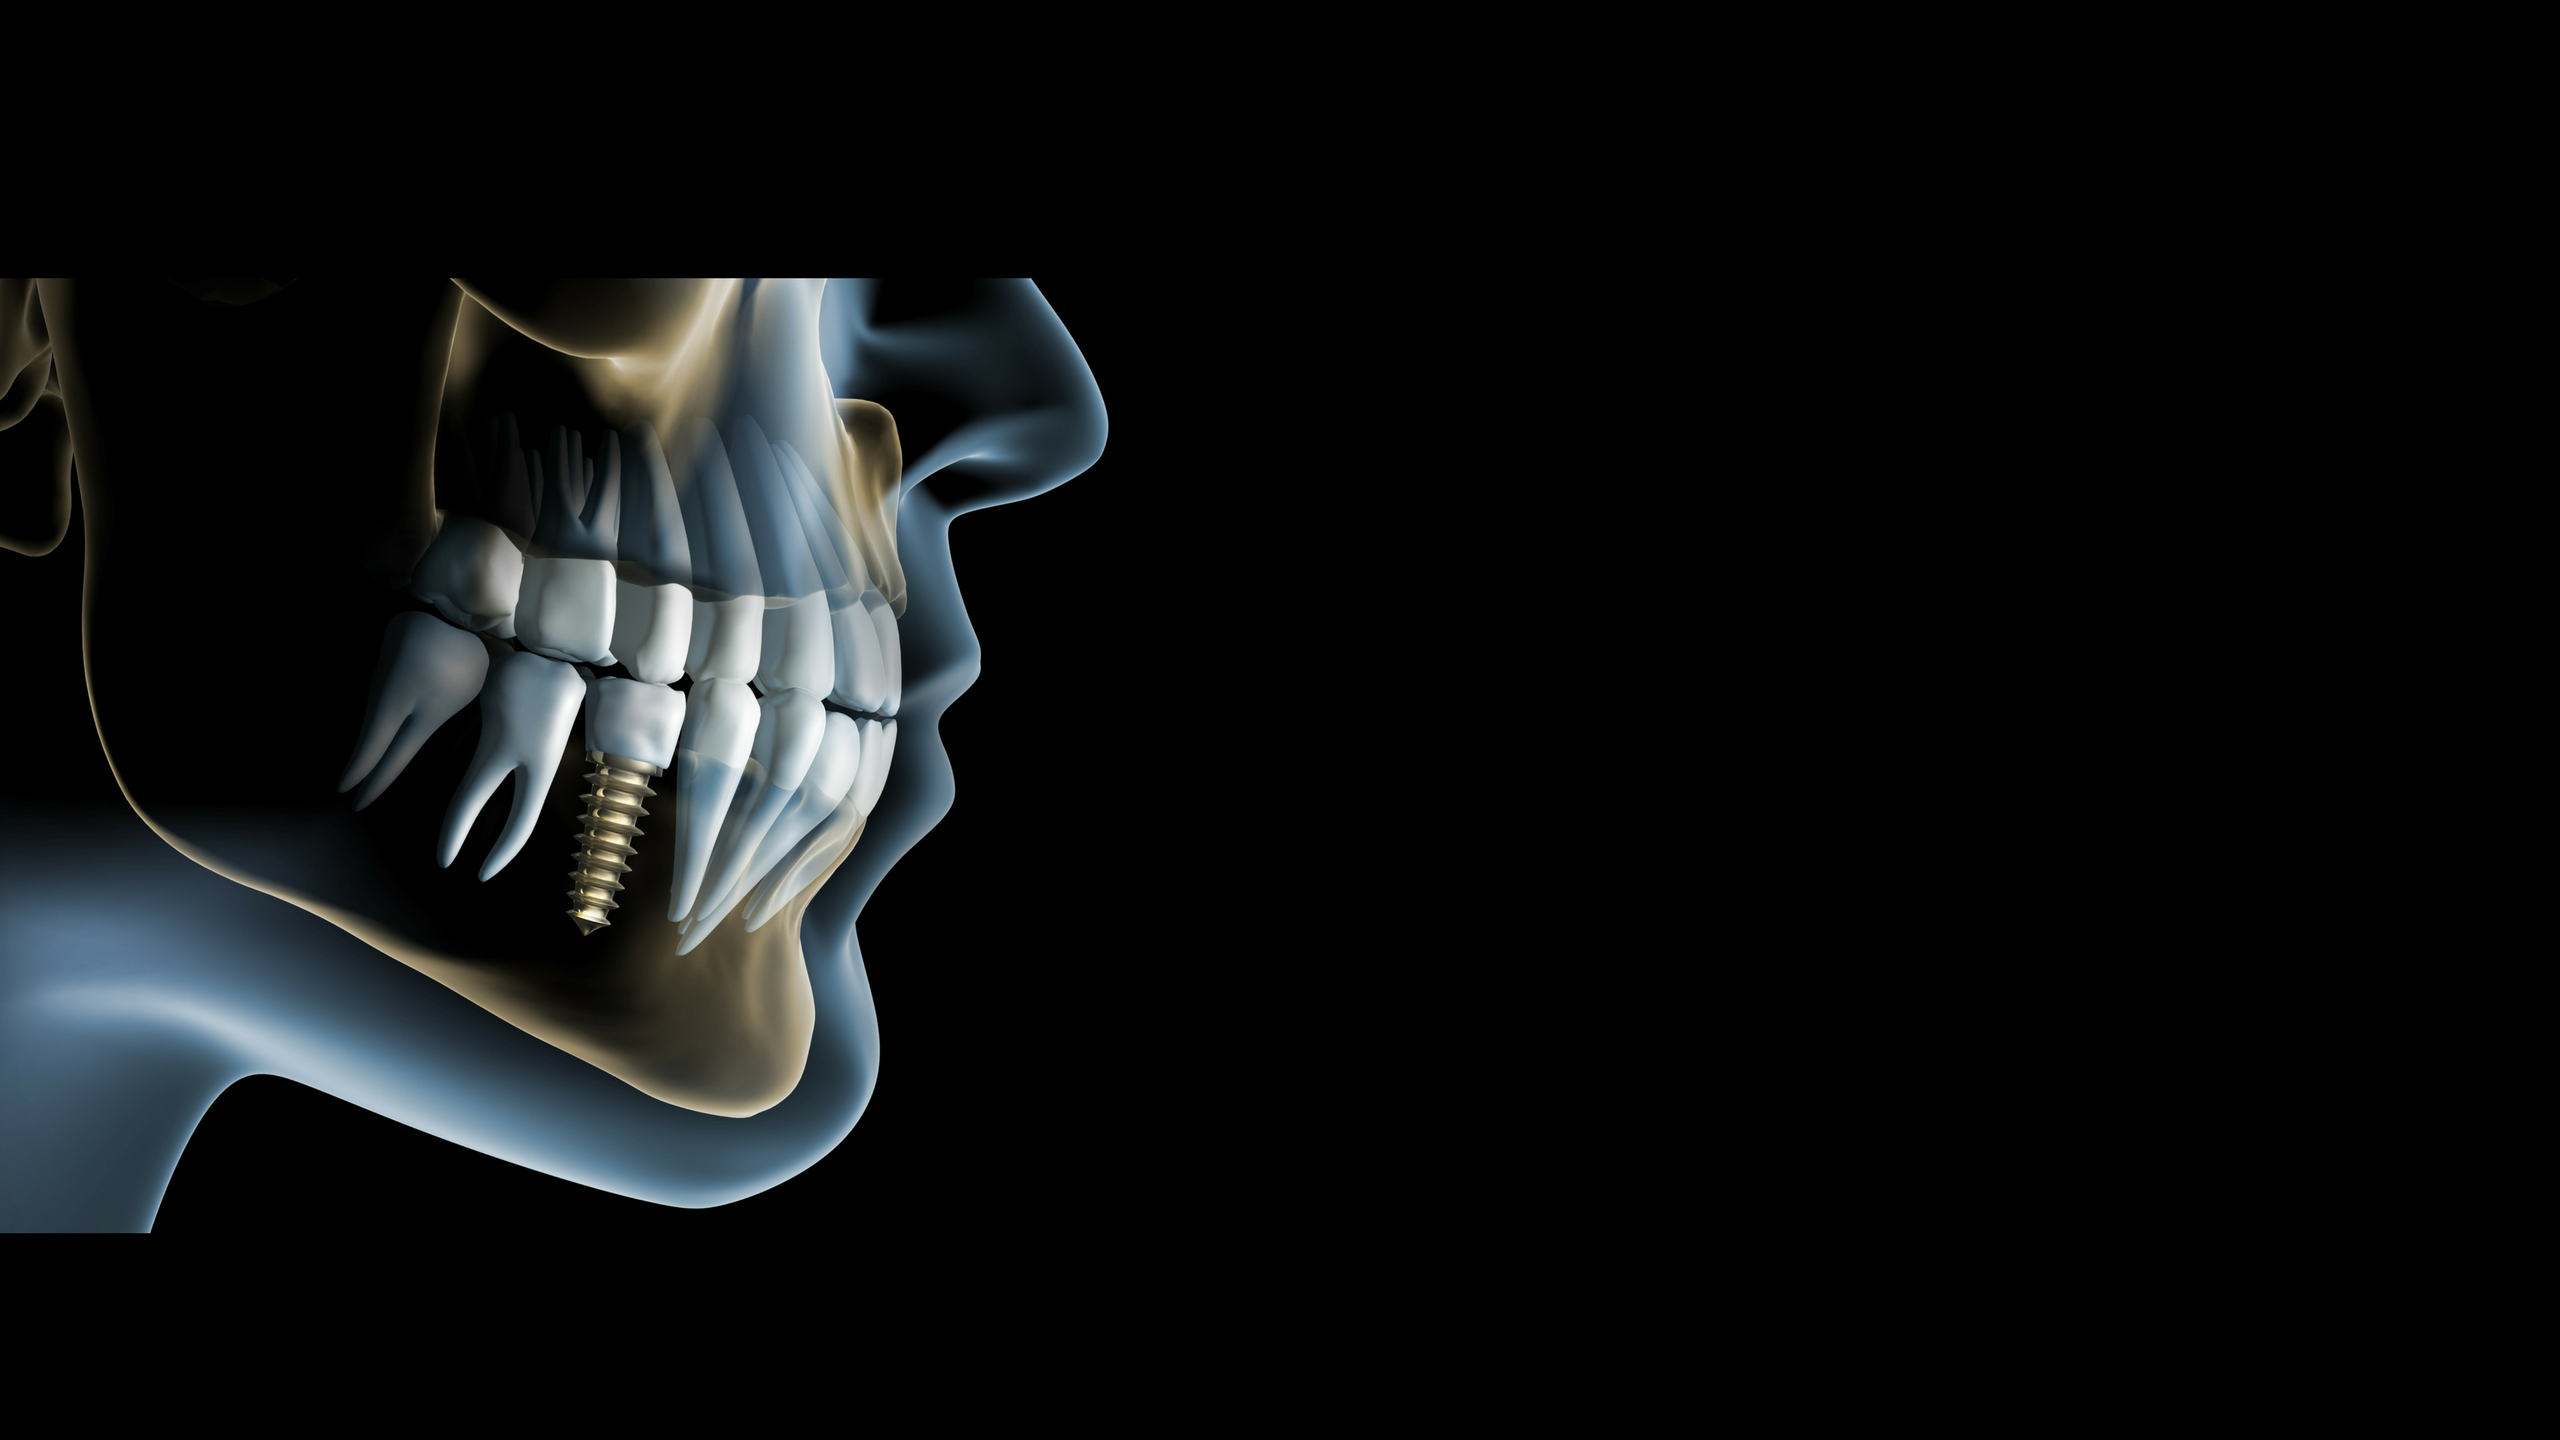

TIPOS DE RADIOGRAFÍAS

EQUIPO ESPECIALIZADO

Contamos con las mejores marcas en equipos de radiografías y tomografías.